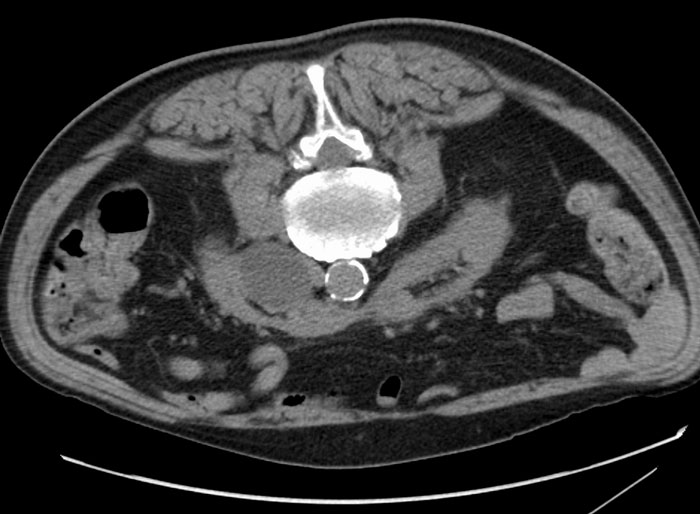

Performing an autopsy on an elderly patient with cardiac valve disease and found a 3 cm white plastic disc lodged in the ostium of one of the renal arteries. It was identical to the disc of the patient's tilting valve type mechanical aortic valve which was in place, intact, and functioning normally. We had no explanation for why an extra valve disc was present far downstream from the heart.

An in depth review of the patient's surgical history revealed that many years prior, during the installation of the patient's aortic valve, the cage for the valve broke while being installed and the disc had flown into the aorta and couldn't be retrieved. The surgeon immediately removed the broken cage, replaced the entire apparatus with another replacement valve and completed the surgery. We found no evidence that there was any subsequent investigation to determine the whereabouts of the lost valve component.

So for years (apparently unknown to most of his caretakers and even potentially to the patient) the patient had a cardiac valve disc lodged in his renal artery ostium, in such a way that it was non-obstructing and stable, and it was discovered as an incidental finding at the patient's autopsy.